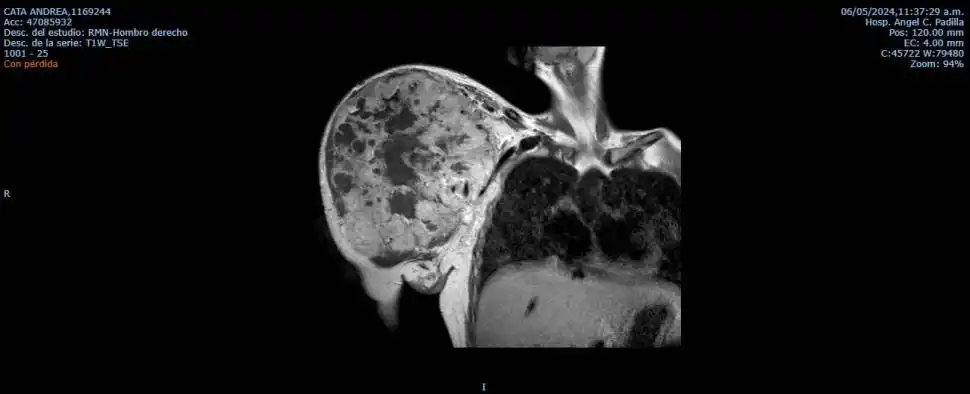

En las fotos que le tomaron por esos días se ve claramente: el tumor en su hombro tenía 30 centímetros de diámetro. Es casi el tamaño de una pelota de fútbol, según le explicaron los médicos.

“Ellos me devolvieron la esperanza y las ganas de vivir”, reconoce Andrea. Desde un comienzo, los profesionales admitieron que estaban ante un gran desafío. El mal que tenía Cata se denomina “tumor de células gigantes”. Se caracteriza por crecer rapidísimo e invadir los tejidos, describieron.

“El tumor era muy agresivo y crecía cada vez más. La paciente ya había hecho quimioterapia y no respondía más a ese tratamiento. Era tan grande que estaba apretando el pulmón y estaba por llegar al corazón. No había opción; teníamos que operarla sí o sí”, repasa López Araujo.